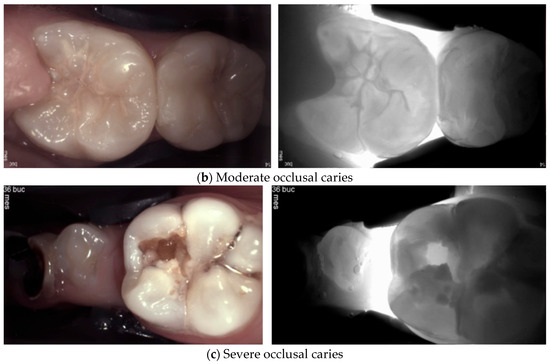

2. Carious Teeth